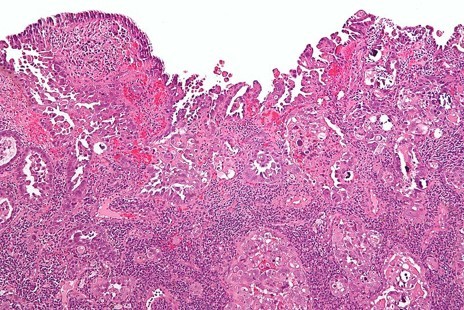

Characterised by a complex papillary (small projections) and/or glandular archietecture with diffuse, marked nuclear pleomorphism

Endometrioid carcinoma are primarily graded by their architecture

Serous carcinoma and clear cell carcinoma are not formally graded